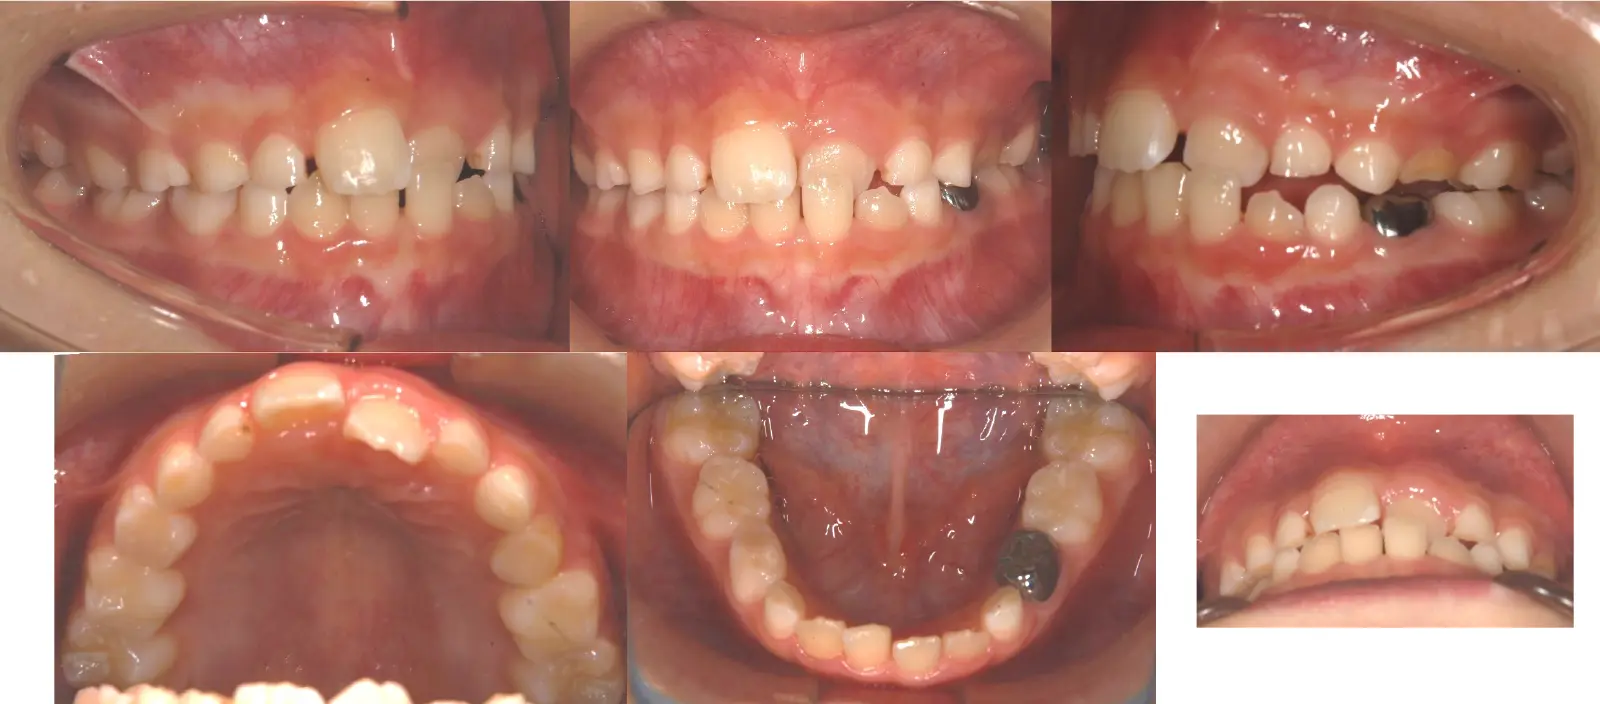

1歯のみの反対咬合

第一段階の治療のみで、

永久歯は問題なく萌出し、安定している

- 主訴

1歯のみの逆破蓋

- 年齢

8歳

- 治療期間

7ヶ月

- 治療回数

5回

- 治療に用いた主な装置

拡大床

- 治療費

400,000円(税別)トータル料金